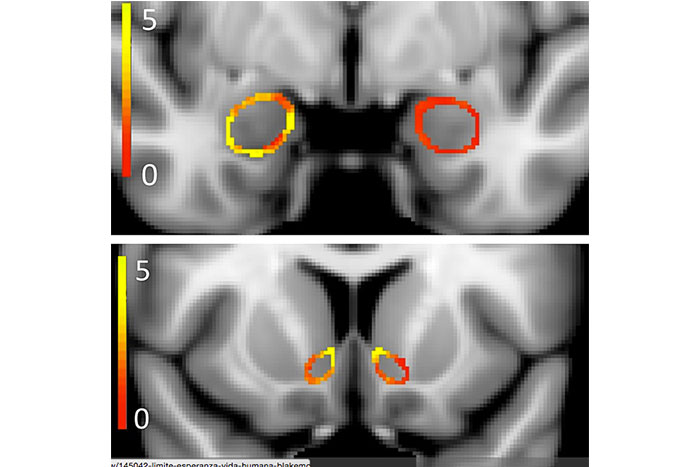

Según una reciente investigación llevada a cabo por las universidades de Harvard y Northwestern, existen además notables diferencias entre los cerebros de los adultos jóvenes fumadores de marihuana y los de los no fumadores.

En el estudio se compararon escáneres cerebrales de fumadores de marihuana de entre 18 y 25 años. Los resultados, según los propios investigadores, fueron sorprendentes, cita el diario 'The New York Times'.

Según el rotativo, incluso en los siete participantes que fumaban solo una o dos veces a la semana se notaron diferencias estructurales en dos regiones importantes del cerebro. Cuanto más fumaban los individuos, mayores eran las diferencias, agrega.